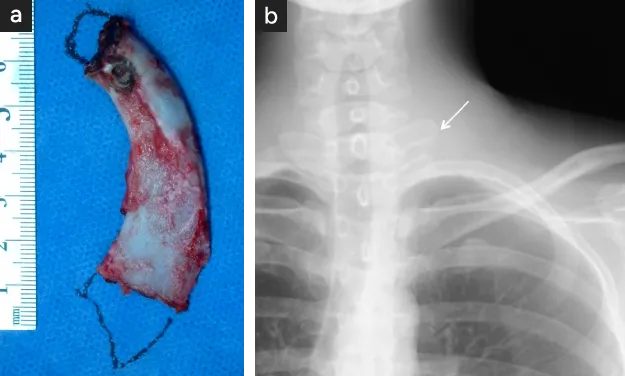

図11

図11. 適切な第一肋骨切除法

• 【切除された左第一肋骨】図の追加部分まで切除され上端は椎体横突起との関節(矢印)

• 術後のX線撮影で、関節(矢印)まで切除されていることが確認される。